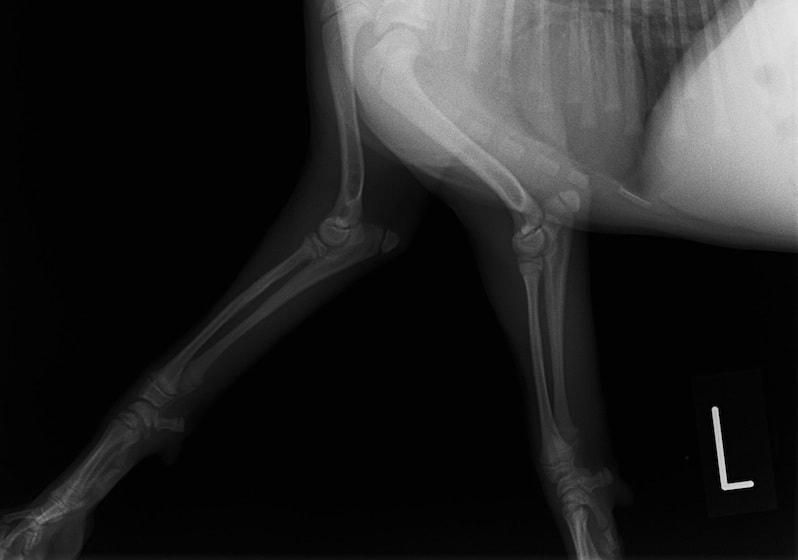

症例3:キルシュナーワイヤーのピンニングによる整復

ペルシャ猫 11ヶ月齢 雄

他院にて左大腿骨遠位の成長板骨折(salter-harrisⅠ型)が認められており、治療相談を目的として来院。当院にて、キルシュナーワイヤーを用いたピンニングにより骨折部位の整復を行いました。術後の経過は良好で、現在も経過観察中です。

術前レントゲン

術後レントゲン